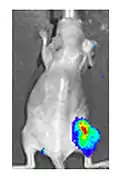

Viral luciferase expression in a mouse tumour

Both in the laboratory and in the clinic it is useful to have a simple means of identifying cells infected by the experimental virus. This can be done by equipping the virus with "reporter genes" not normally present in viral genomes, which encode easily identifiable protein markers. One example of such proteins is GFP (green fluorescent protein) which, when present in infected cells, will cause a fluorescent green light to be emitted when stimulated by blue light.[87][88] An advantage of this method is that it can be used on live cells and in patients with superficial infected lesions, it enables rapid non-invasive confirmation of viral infection.[89] Another example of a visual marker useful in living cells is luciferase, an enzyme from the firefly which in the presence of luciferin, emits light detectable by specialized cameras.[87]